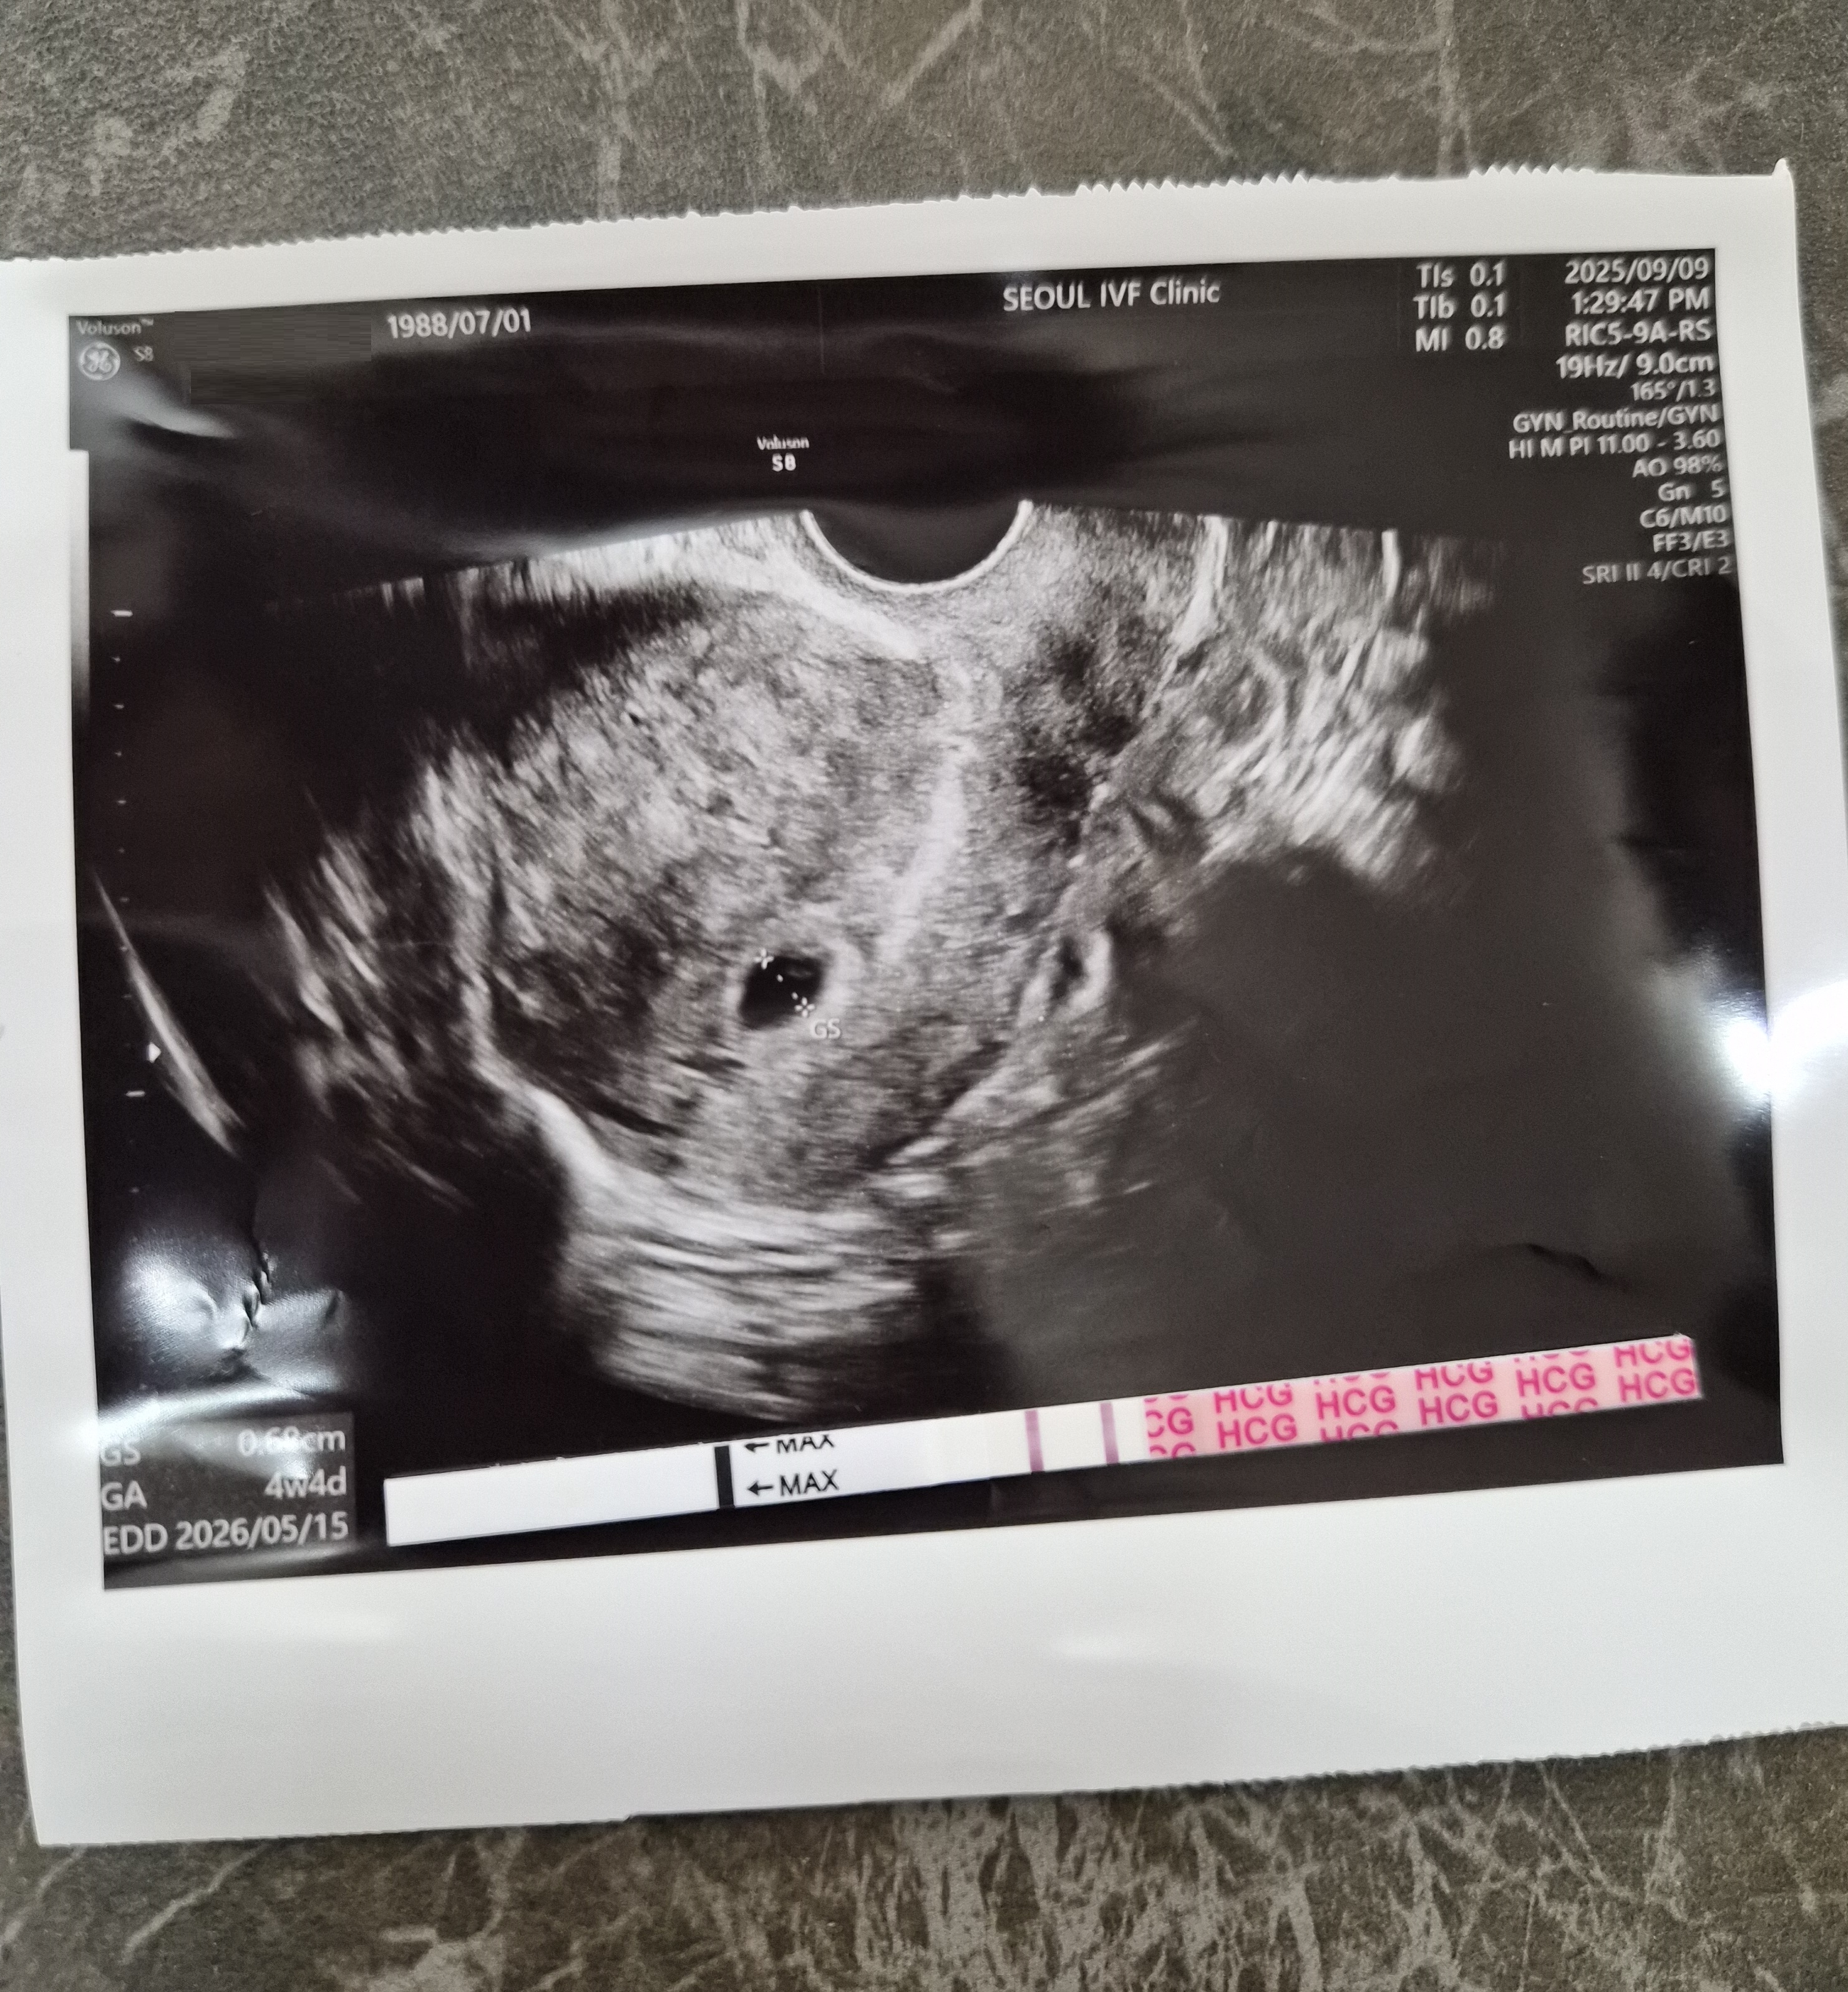

| 가슴 떨리는 임신 이야기를 공유해 주세요. | 결혼 전부터 계획임신을 시도했지만 실패했고, 결혼 후 선근증 수술까지 했지만 자연임신이 되지 않아 서울IVF를 찾게 되었습니다. 그러다 인공수정 1차, 시험관 1차에 첫째를 얻고, 첫째가 25개월 되었을 때는 시험관 2차 만에 둘째를 만나게 되었어요. 아이들의 첫 심장소리를 들었을 때 그 떨림과 감동은 평생 잊을 수 없습니다. |

| 치료 도중 느꼈던 가장 기뻤던 순간과 절망적인 것들은 무엇인가요? 잊지 못할 경험이 있나요? | 가장 기뻤던 순간은 두 아이 모두 첫 심장소리를 들었던 순간이었어요. 반대로 가장 절망적이었던 때는 둘째를 준비하던 과정에서 시험관 1차가 실패했을 때였습니다. |